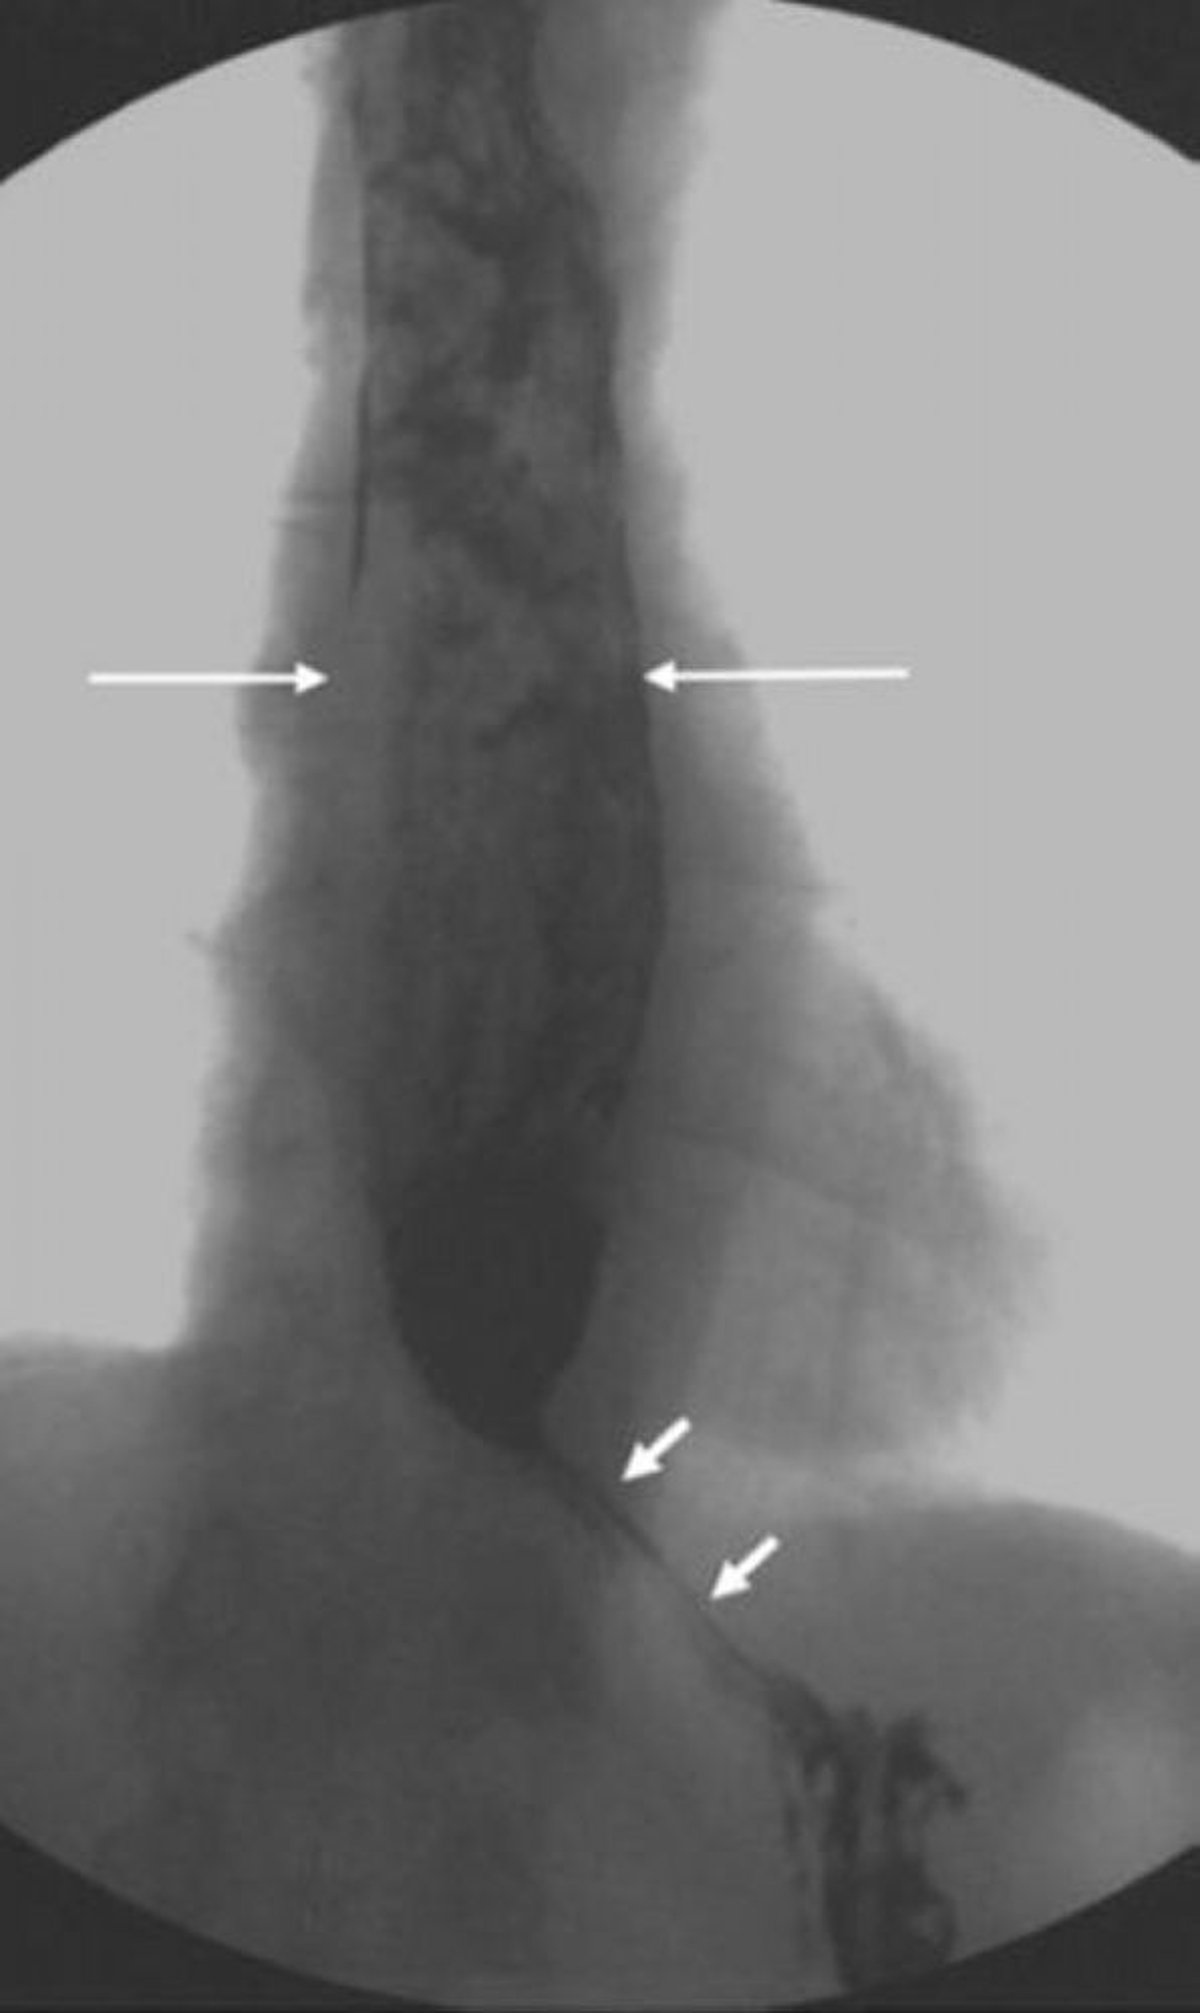

Trago de bario que muestra un esófago dilatado con un esfínter esofágico inferior más estrecho y en forma de pico

Esta imagen muestra acalasia con dilatación esofágica proximal y relajación incompleta del esfínter esofágico inferior. Obsérvese la apariencia no homogénea del material dentro del esófago dilatado debido a la presencia de alimentos no digeridos que no pasaron al estómago (flechas largas). En la acalasia grave, solo pequeñas cantidades de medio de contraste pueden pasar a través de la unión esofagogástrica en forma de pico (flechas cortas).